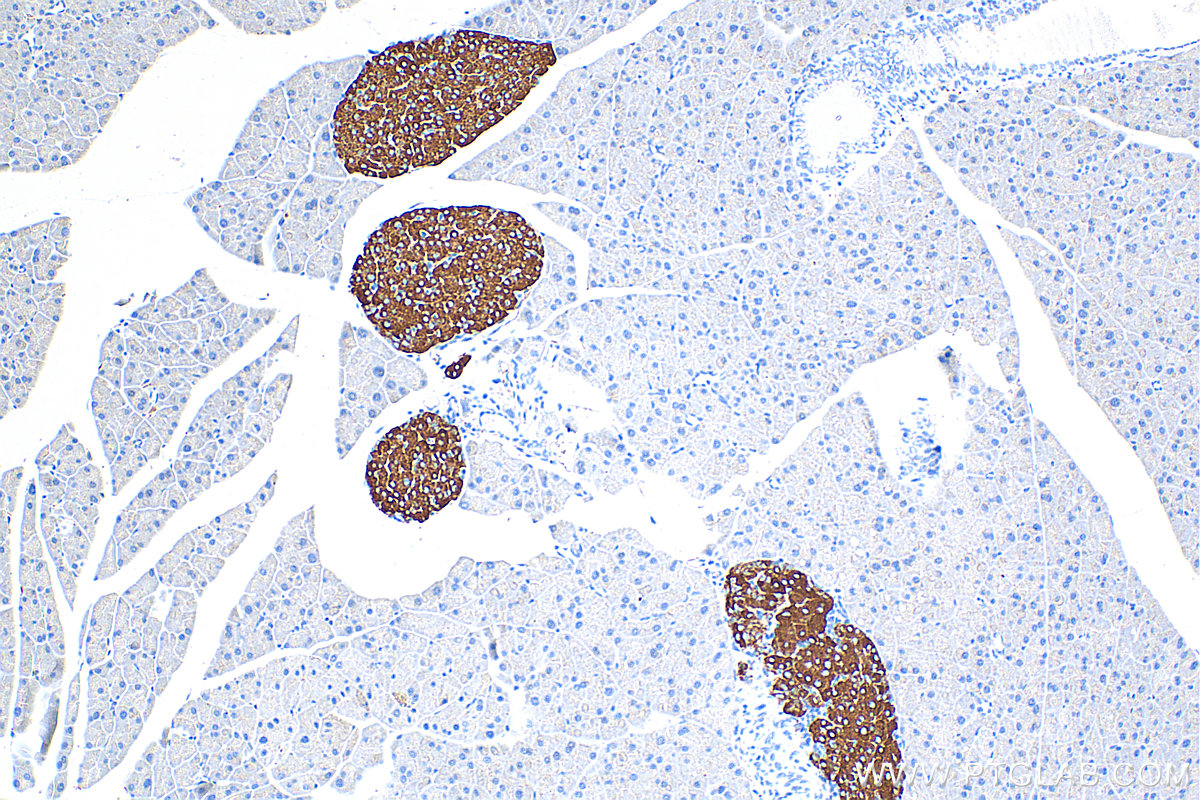

| Positive IHC detected in | mouse pancreas tissue, mouse brain tissue, human brain tissue, ganglioma tissue, human pancreas tissue, neuroblastoma tissue, human pituitary adenoma tissue Note: suggested antigen retrieval with TE buffer pH 9.0; (*) Alternatively, antigen retrieval may be performed with citrate buffer pH 6.0 |

Synaptophysin (SYP, also known as major synaptic vesicle protein p38) is a 38-kDa integral membrane glycoprotein that regulates synaptic vesicle endocytosis. It is the most abundant synaptic vesicle protein by mass. Synaptophysin is present in neuroendocrine cells and neurons that participate in synaptic transmission. Synaptophysin is a useful marker for the identification of neuroendocrine cells and neoplasms. Synaptic proteins, including synaptophysin, are reduced in brain tissue from patients with Alzheimer's disease. (PMID: 3010302; 21658579)